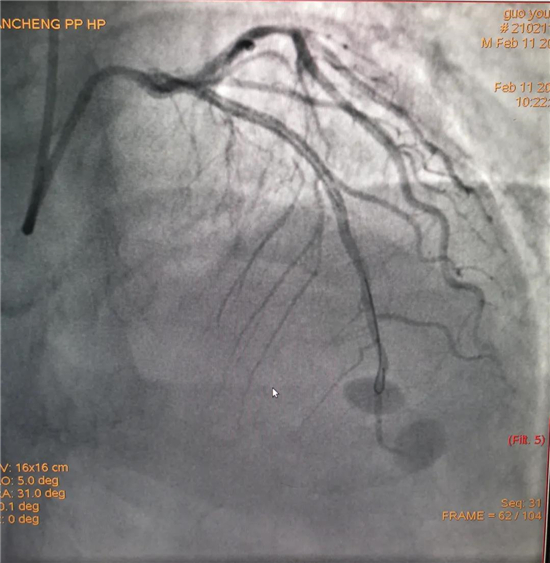

除夕,郭先生無明顯誘因突發胸痛,120急救人員到達現場,心電圖顯示:竇性心律完全性束支傳導阻滯。信息立刻發送到胸痛中心介入微信群中,心內科值班醫生初步診斷為急性廣泛前壁心肌梗死,必須盡快進行急診支架治療,開通血管。值班醫生電話指導院前治療,并立即啟動胸痛綠色通道,24小時備班的介入治療團隊立即到位,9:30患者被送到導管室行冠脈介入診療,9:40急診PCI手術隨之開始,冠脈造影檢查提示左前降支閉塞,植入支架,堵塞的血管被順利打通,患者癥狀緩解,手術非常成功,10:20患者被送往病房進一步治療。

大年初一,王女士在中午休息時無明顯誘因出現上腹部疼痛,伴瀕死感、大汗、劇烈嘔吐,當地診所以“胃炎”治療無緩解,自行來我院就診。在急診內科快速完成心電圖等相關檢查后,心電圖示:竇性心律,部分導聯明顯異常,經心內科值班醫生初步診斷,該患者為急性冠脈綜合征,與患者家屬溝通行急診PCI的相關事宜,溝通中了解患者高血壓、2019年因急性心肌梗死在周口市中心醫院性急診冠脈介入植入1枚支架等高風險因素。風險與生命孰重,21:50 患者到導管室行急診PCI治療,造影提示右冠閉塞。22:18 導絲通過閉塞段,后植入支架一枚,血管再通。22:45手術結束,送往CCU觀察治療。